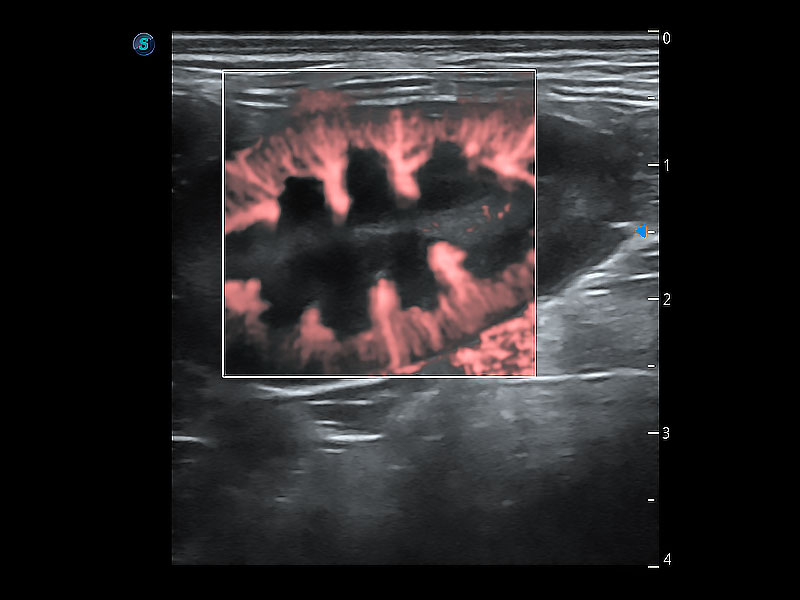

(犬)胎儿主动脉弓立体血流

(犬)肾脏显微血流